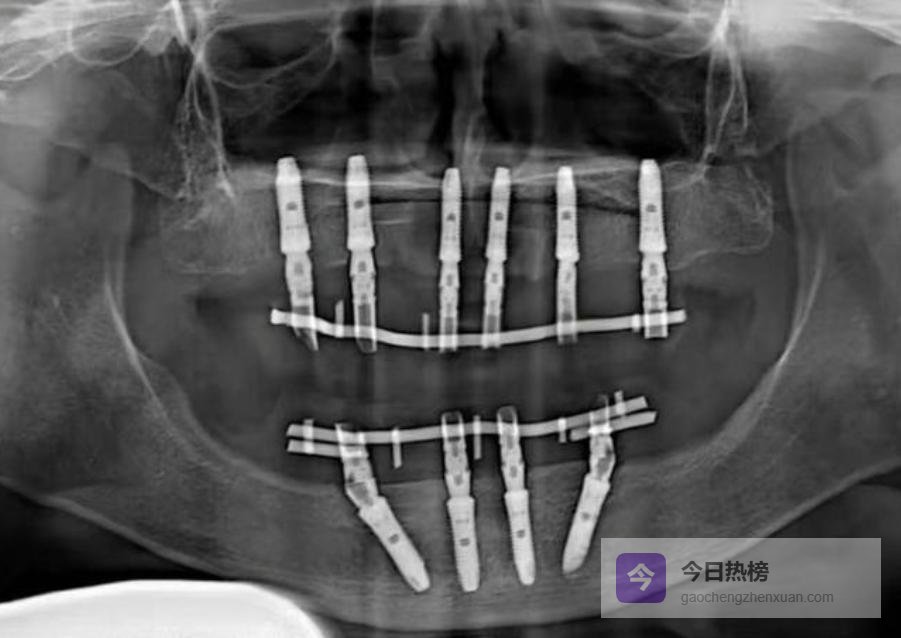

二、术前准备篇:拍片、骨粉、医生选择第4条:术前一定要拍全口CT。 普通牙片根本看不清神经管和牙槽骨的细节,十年前我就见过医生盲种伤到神经的案例,后果特别严重。别为了省几百块拍片费,拿自己的神经开玩笑。

第5条:牙槽骨太薄,一定要先补骨粉。 骨厚度不足3毫米,千万别强行种植。尤其是那些鼓吹“当天种当天走”的机构,大概率是不顾条件硬操作,风险极高。记住:骨量不够就老老实实植骨,别心急。